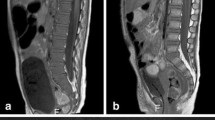

3-month-old boy presenting with inspiratory stridor due to thoracic tumor (a; white arrow) located in the posterior mediastinum with extension in the neuroforamen Th3–Th4 (open arrow). With ultrasound-guided biopsy, a neuroblastoma, standard risk was diagnosed. The bone marrow biopsy appeared normal. At presentation diffuse low T1 signal of the bone marrow is seen, isointense compared to the intervertebral disc (b with zoomed insets; white arrowhead indicating the intervertebral disc) and muscles consistent with red bone marrow. Furthermore, the signal intensity of the bone marrow at the sagittal STIR is within normal limits (c). With watchful waiting spontaneous regression of the tumor was observed (d; white arrow) and no treatment was necessary. After 6 months, there is a marked decrease in size of the tumor (d; white arrow) with increased T1 signal intensity related to internal calcifications. Furthermore, the bone marrow signal showed an increase in signal intensity (e with zoomed insets), especially centrally within the vertebral body consistent with areas of fatty bone marrow. The signal intensity at the sagittal STIR of the spine is within normal limits (f)

Sagittal T1-weighted (a) and short tau inversion recovery (STIR) (b) in the same patient as Fig. 7.11, illustrating the bone marrow metastases in several thoracic and lumbar vertebral bodies (white arrows)